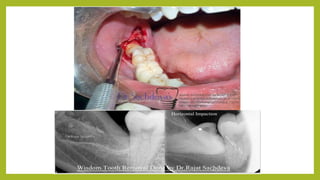

DIAGNOSIS • Proper consultationand check up with the dentist. • X-ray for checking the position of the erupting tooth.

AVAILABLETREATMENT OPTIONS • Irrigationwith medicated solution of the infected site. • Local application of anesthetic agent to educe the pain. • Antibiotic and analgesic course if required. • Operculectomy if required. • Extraction of the impacted tooth